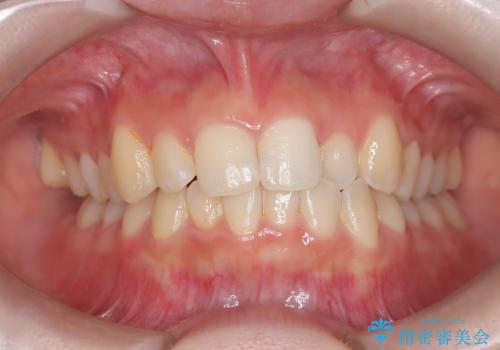

【インビザライン】前歯を下げたい。

- 前歯が出ていることを主訴に来院されました。

下顎前歯が1本欠損していることもあり、前突はある程度残ることを説明し、インビザラインにて治療を行いました。

今回は抜歯矯正ではなく歯列弓の拡大とIPR、遠心移動を行って配列することができました。

口元も改善し患者さんには喜んでいただけました。

下顎前歯が1本少ないため、上下の正中は合いません。